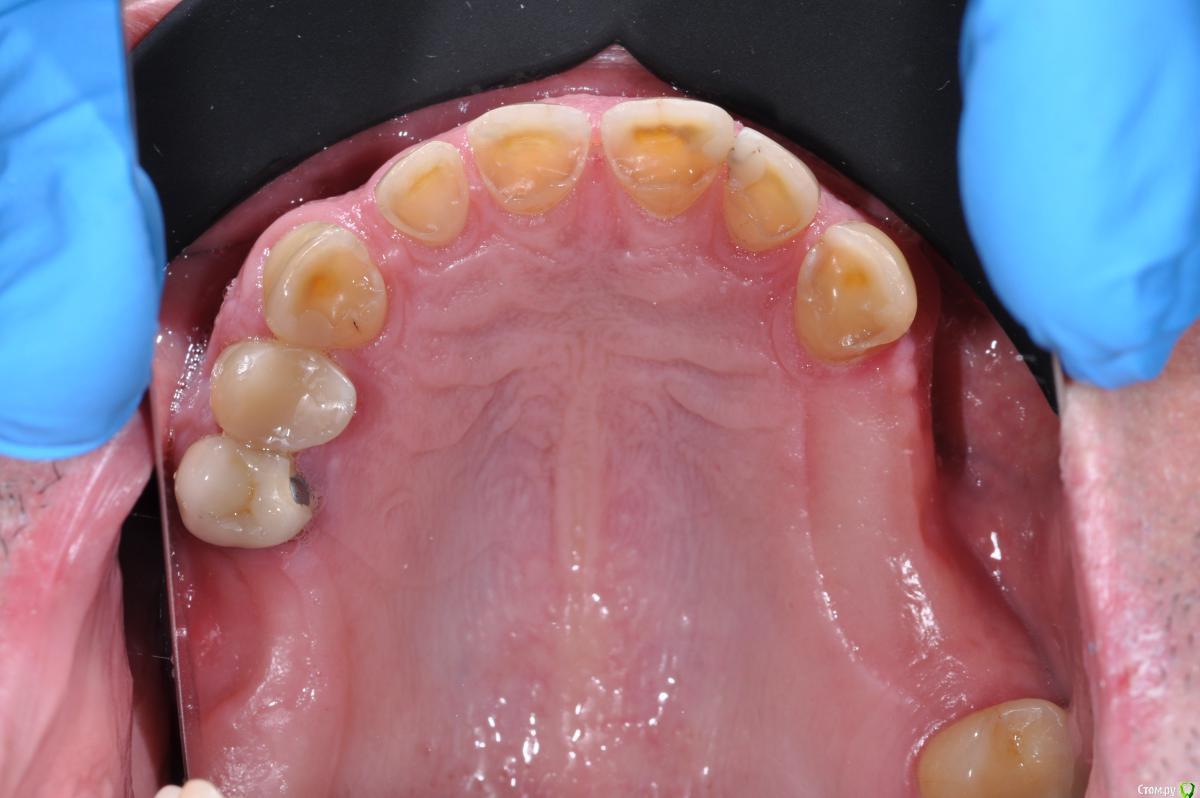

Neilrus Опубликовано 24 января, 2019 Поделиться Опубликовано 24 января, 2019 Здравствуйте, коллеги. Вопрос по выбору типа реставрации, есть пациент с полностью несъемным низом, а вот на верхней челюсти посмотрите на фото и снимок, пожалуйста, 17зуб, потом 13-25. Имлантация на верхней челюсти в ближайшие годы не предвидится по ряду причин. отработали пациента на капах, утвердили мокап, скоро начнем. Стираемость изнутри восстановлю композитом и обработаю под коронки. Вопрос по типу коронок, хочется и красиво и надежно.Верх: Понятно что если иметь ввиду что это мужик с такой объемной потерей тканей, да еще со съемником, то центр желательно цирконий, может даже преттау, но адгезия плохая пугает, да и внешний вид даже с хорошим техником не очень.Дисиликат с нанесением? Как вы считаете, выдержит?Гипертонуса нет, не бруксист, будет каппа ночная на низ, конечно Низ: Тут выбор между коронками и винирами (не на огнеупоре ,а обычные)жевательные низ пока временные, потом выведу их по плоскости, там emax без нанесения будут и цирконий на импл. Как бы поступили вы? Ссылка на комментарий